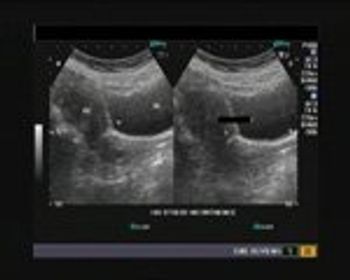

These ultrasound images show right hydroureter with hydronephrosis. What else do you see and what is the cause?